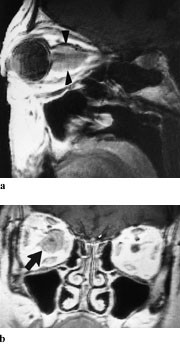

CT viser homogen fortykkelse av synsnerven både i aksial- og koronalplan. Hvis CT benyttes, hører koronale snitt med, og man bør undersøke uten og med intravenøs kontrast. Selve nerven kan ikke sees som en separat struktur, ikke engang etter kontrast. Utvidelse av optikuskanalen er vanlig. MR viser enten fusiform, eksentrisk eller tubulær fortykkelse (fig 5a). T1-vekting viser lik intensitet mellom tumor og nerven, mens T2-vekting viser økt signal. Kontrastopptaket er ofte beskjedent. Ved intrakranial utbredelse sees fortykkelse av chiasma, med lav signalintensitet på T1- og økt signal intensitet på T2-bilder (fig 5b). Fettsuppresjonsteknikk er nødvendig for å skille kontrastoppladning i tumor fra høyt signal i orbitalt fett.

CT viser diffus fortykkelse av synsnerven, med kraftig kontrastopptak i tumor. Forkalkninger styrker differensialdiagnosen. Det er vanskelig å påvise kalk ved MR, og derfor er begge metodene til nytte. Ved MR har svulsten lavere intensitet enn selve synsnerven (fig 6 a). Små meningiomer kan som regel påvises bare ved bruk av gadoliniumkontrast, og gir kraftig kontrastoppladning (fig 6 b). Denne metoden fremstiller også best eventuell intrakranial utbredelse av tumoren (7). Den beinete optikuskanalen kan være utvidet. Ordinære skjelettbilder av foramen optici er i dag oftest erstattet av tynne CT-snitt i to plan.